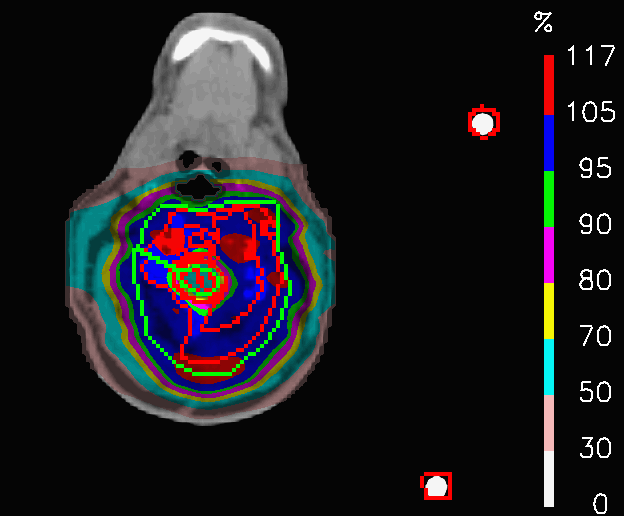

By comparing the dose distributions of PLAN-NOM and PLAN-OL-1 at the level of the shoulders in Fig.14, it is noticeable how the dose in PLAN-OL-1 results better confined inside the CTV. This fact determines a remarkable improvement in the sparing of the esophagus and the spinal cord, as reported in Table 4 and in Fig.15, where the comparison between the cumulative DVHs of the two plans are shown. No relevant changes concern the coverage of the target volume, since 𝐃𝐦𝐞𝐚𝐧subscript𝐃𝐦𝐞𝐚𝐧\mathbf{D_{mean}} differs by 0.3% from the nominal plan. These results clearly show that switching off the posterior fields at the level of the shoulders allows to achieve a better sparing of some OARs, while keeping the same irradiation level for the tumour.

Refer to caption

(a) PLAN-NOM

(b) PLAN-OL-1

Figure 14: Head and neck tumour: dose distributions of PLAN-NOM and PLAN-OL-1 at the level of the shoulders.